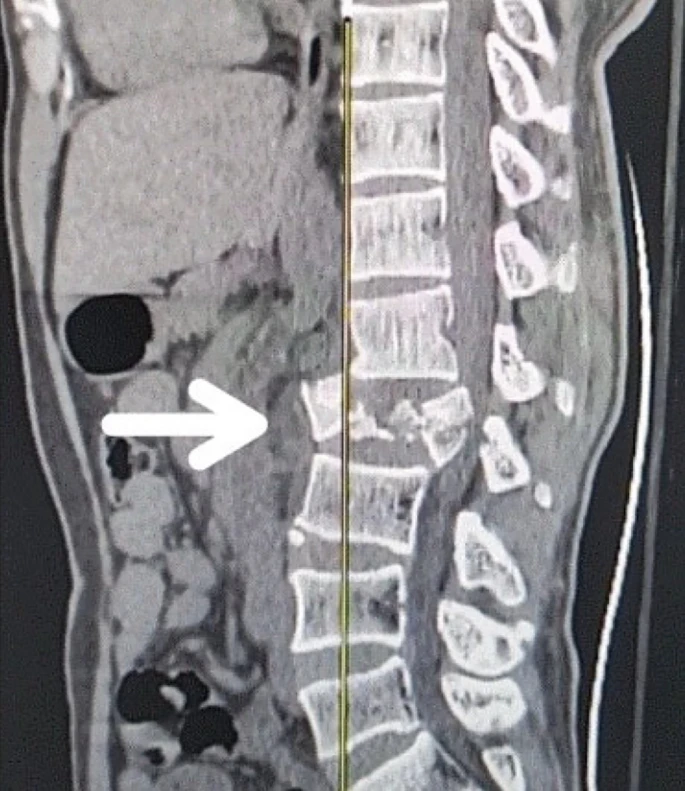

創(chuàng)傷性脊髓損傷是由于脊柱受到突然的強力撞擊,導致椎骨骨折、脫臼、擠壓或壓縮(圖1)。主要原因包括機動車事故,其中汽車和摩托車碰撞占每年新增脊髓損傷病例的近一半。跌倒,尤其是65歲及以上人群的跌倒,是造成脊髓損傷的重要原因,約占60%。體育活動,例如沖擊性運動和淺水潛水,約占此類損傷的10%。

慢性期開始于損傷后約3-6個月,并持續(xù)患者的余生,典型特征是囊腫形成和嚴重的神經膠質瘢痕(圖2)。